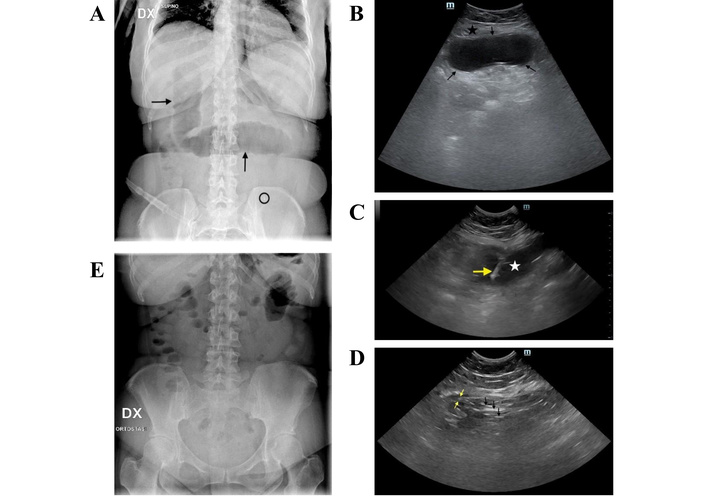

A 42-year-old woman was admitted to the emergency room for acute abdominal pain. Four months before, an EIGB had been delivered for weight loss. On physical examination, the patient had a distended abdomen with marked tenderness in the lower abdomen, but without rebound or guarding. Abdominal plain X-ray showed the small radiopaque marker of the EIGB in the left inferior abdominal quadrant and dilation of small bowel loops (Figure 1A). At US, the deflated EIGB was easily identified under the umbilical line just below the abdominal wall (Figure 1B).

Case 1. (A) Plain X-ray of the abdomen at admission: dilated bowel loops are visible in the mid-abdomen (black arrows), and a radiopaque marker—indicating the presence of the EIGB—appears in the left lower quadrant (black circle). (B) Transverse ultrasonography (US) scan of the hypogastrium shows an oval anechoic structure with hyperechoic (bright) walls (between black arrows) just beneath the rectus abdominis muscle (black star). (C) Transverse US scan of the hypogastrium: the yellow arrow indicates the needle tip inside the nearly completely deflated balloon (white star). (D) Transverse US scan of the hypogastrium: at the end of percutaneous aspiration, only multiple hyperechoic strands (black arrows), representing overlapping walls of the balloon, are observed. The wall of a bowel loop is also seen (yellow arrows). (E) Plain abdominal X-ray taken 24 hours after admission demonstrates resolution of the mechanical ileus.

The patient was rehydrated, and a nasogastric tube was inserted. Given the absence of peritonitis and to avoid surgical intervention, a minimally invasive percutaneous approach was selected. Informed consent was obtained from the patient before the interventional procedure.

After local anesthesia with 5 mL of 2% lidocaine, an 18-gauge Chiba needle was introduced into the impacted EIGB (Figure 1C) under continuous real-time guidance; then, 250 mL of clear, viscous liquid was quickly aspirated.

During aspiration, the balloon progressively collapsed until multiple, overlapping hyperechoic linear strands signaled the complete deflation of the EIGB (Figure 1D).

No complications ensued. Six hours later, the patient reported watery diarrhea, a sign of excretion of the EIGB. Abdominal plain X-ray at 24 hours confirmed the resolution of ileus and the absence of the EIGB radiopaque marker (Figure 1E).